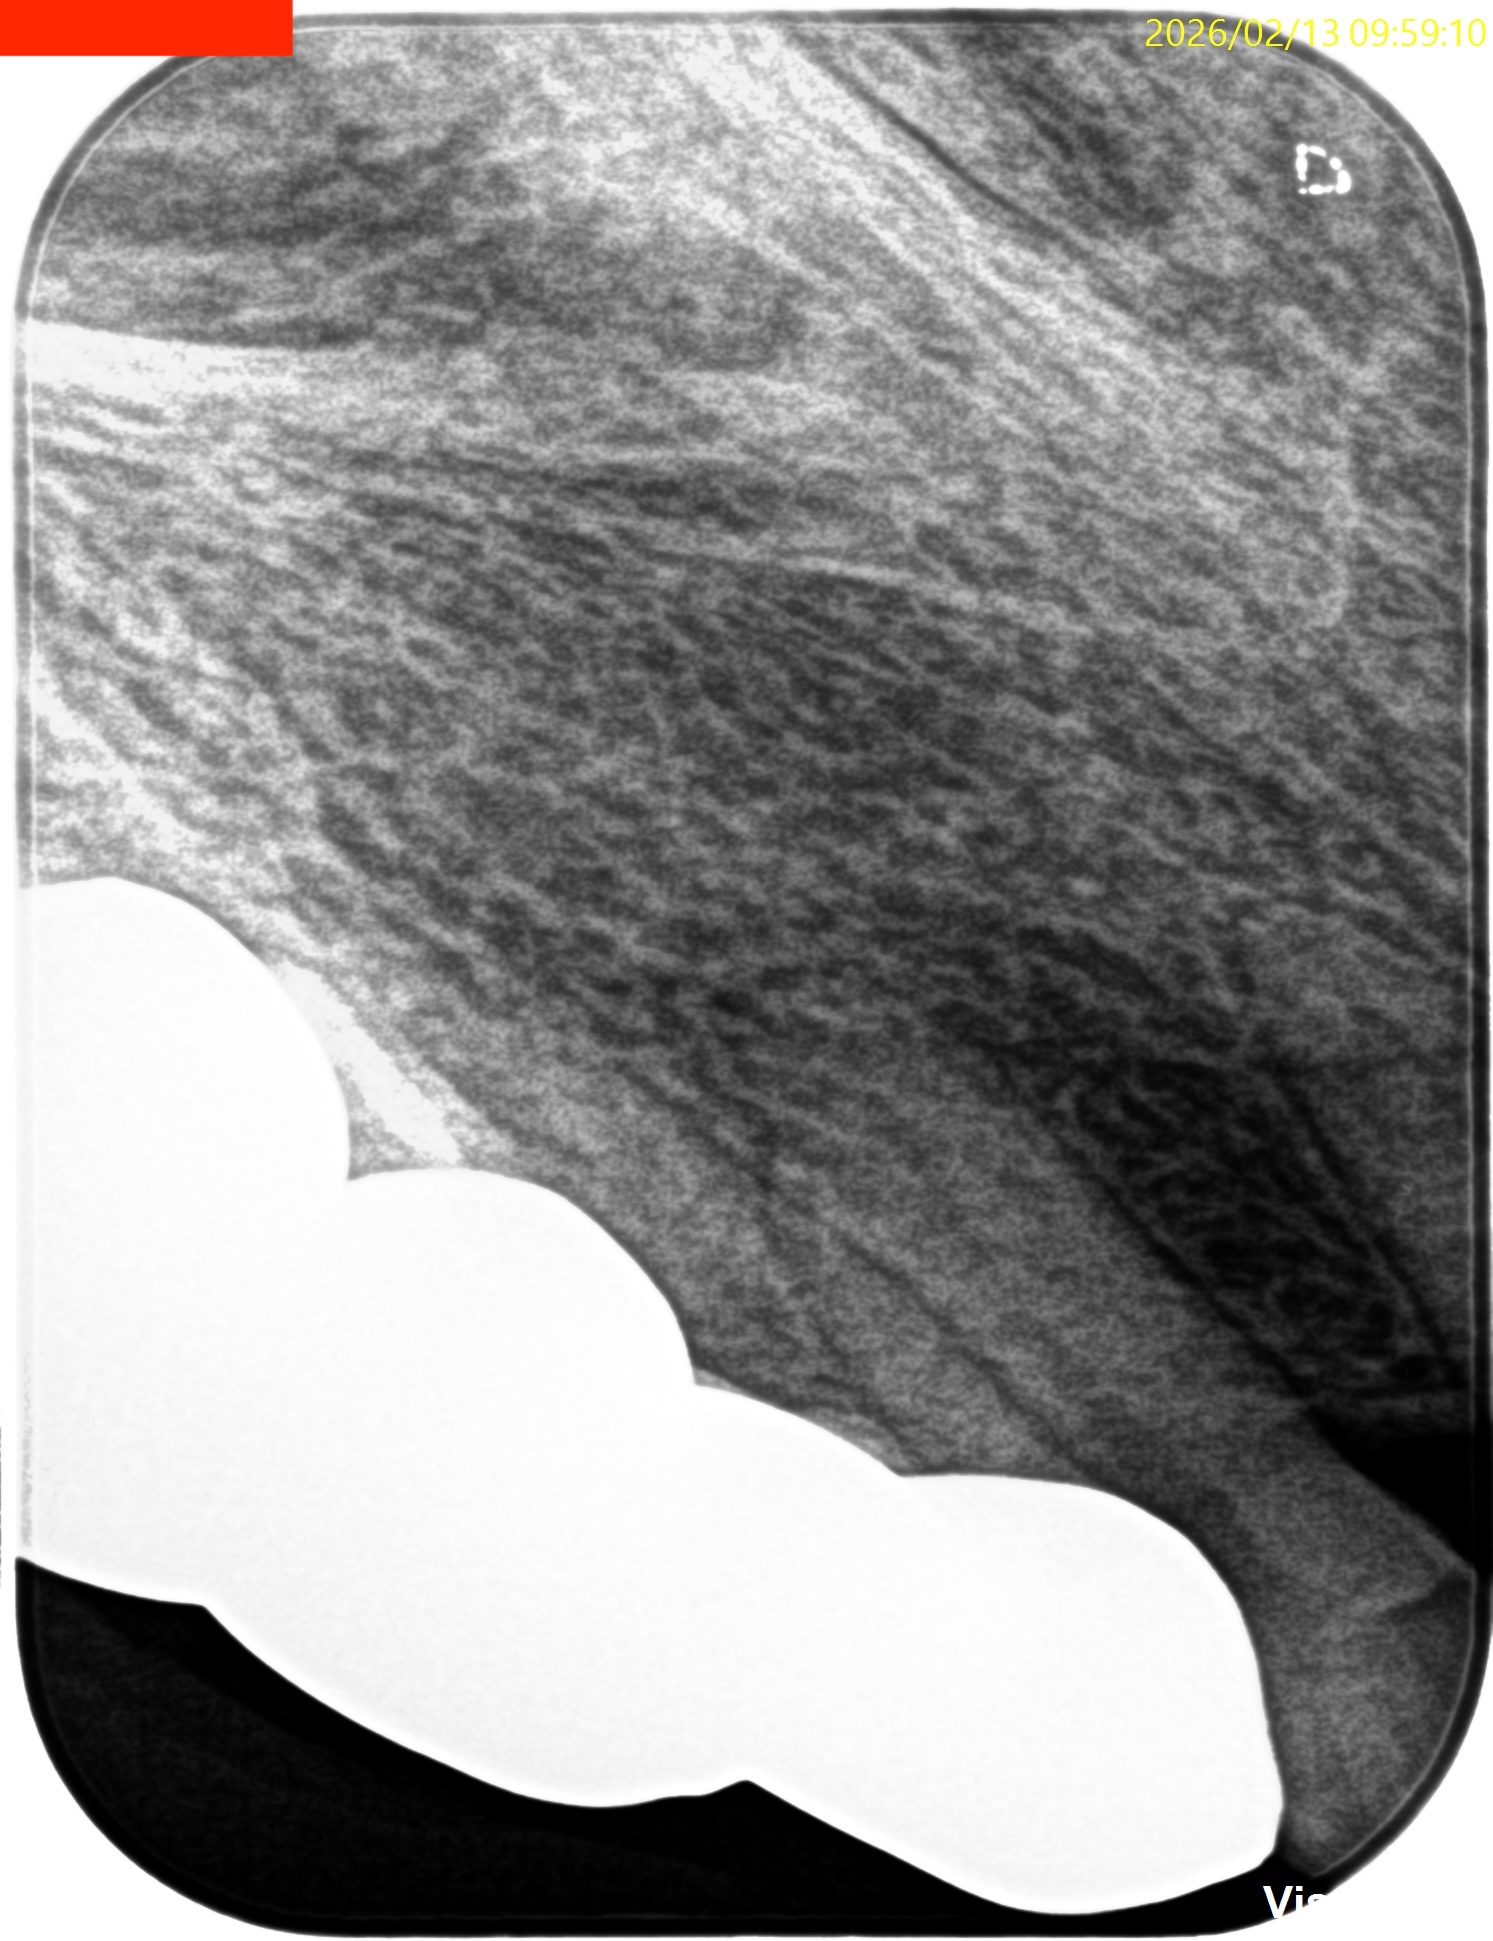

PA, CBCTを撮影した。

#6 Invasive Cervical Root Resorption Repair, Apicoectomy 4M recall(2026.2.13)

根切した部分にはだいぶ骨が添加されているし、外部吸収も進展していないようだ。